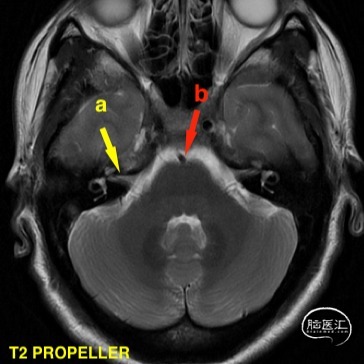

头颅MR(2021-07-23),面听神经复合体未见明显血管压迫。

a 黄色箭头为患侧面听神经复合体 b 红色箭头为动脉成像